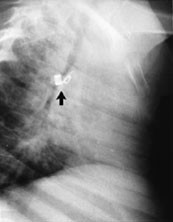

Lukking av ductus med spiral er en nyere teknikk (4). Vi har benyttet Cooks fiberbelagte stålspiraler for bruk i ductus (fig 2) og applikert dem perkutant, i de aller fleste tilfeller antegrad gjennom et 5 french innføringskateter. Størrelse og antall vindinger blir bestemt etter forutgående aortografi. Spiralen er skrudd fast på føringsvaieren, og kan derfor trekkes inn i føringskateteret igjen og omplasseres til posisjonen er tilfredsstillende. De fleste vindingene av spiralen settes i ductus" infundibulum. Deretter utvikles de siste én til halvannen vindinger på pulmonalarteriesiden. Etter tilfredsstillende angiografisk kontroll skrur man spiralen fra føringsvaieren.